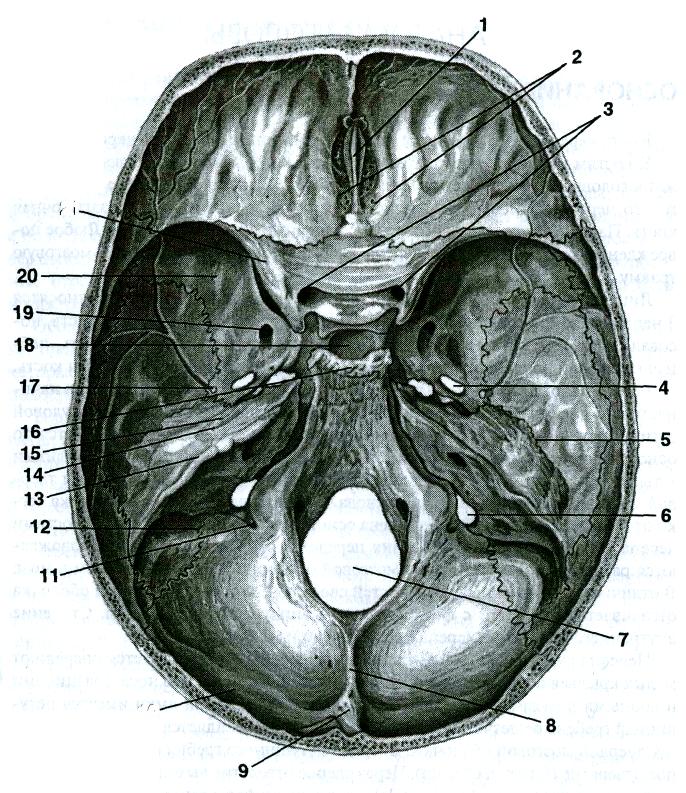

Необычные объекты: Переднее продырявленное вещество

Раздел: Альбом открытий